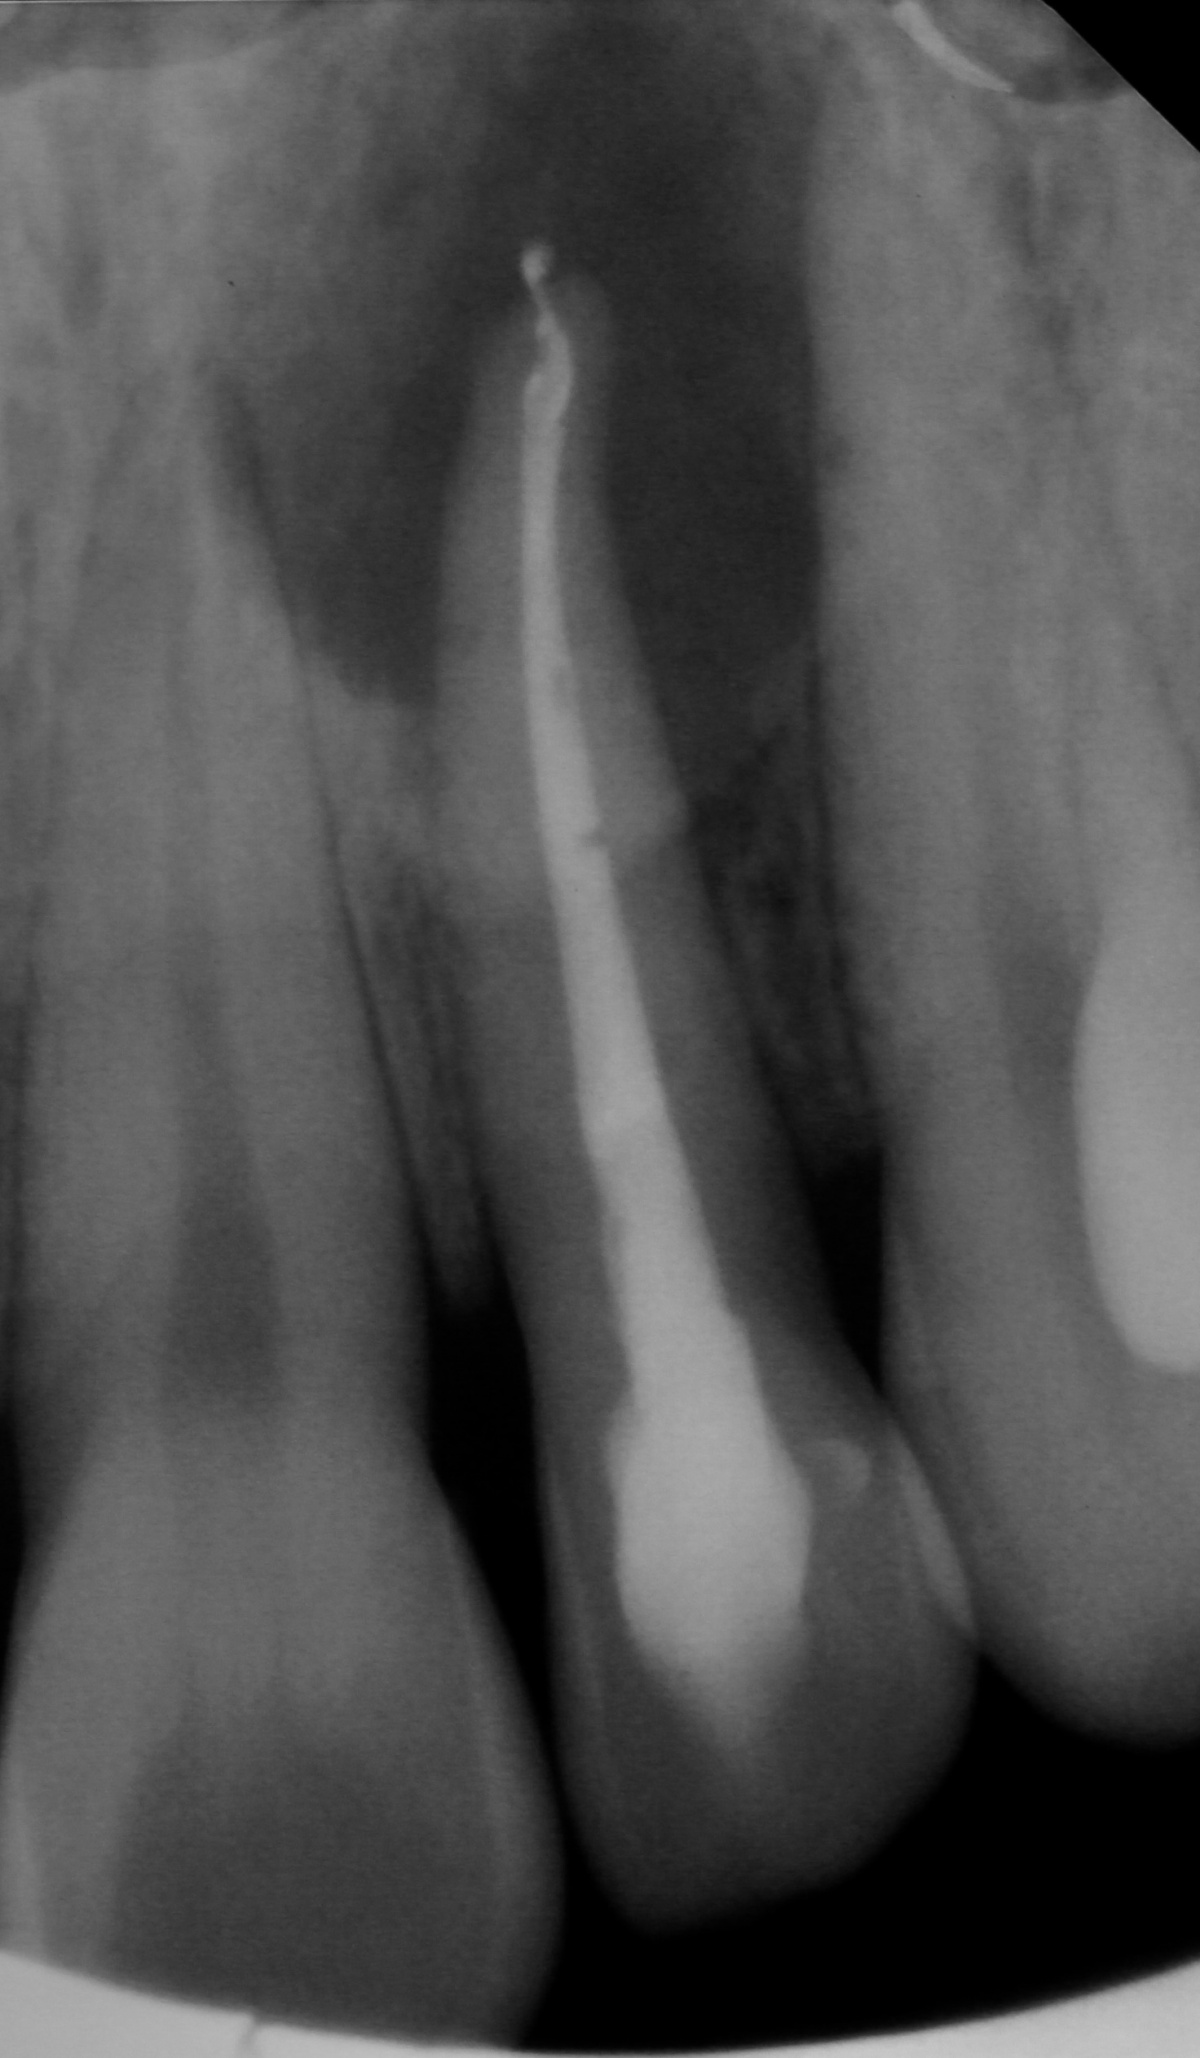

Zahn 21, Hinweise auf möglicherweise

überpresstes Wurzelfüllmaterial im apikalen Bereich.

Wurzelfüllung sowie Hinweise auf eine vorhandene

Via falsa.

Im Januar 2019 stellte sich ein 52-jähriger Soldat mit einem auf Gingivaniveau abgebrochenen Zahn 21 im Rahmen einer Notfallbehandlung bei uns vor. Zur Wiederherstellung der Ästhetik, Phonetik und Beißfunktion wurde die Krone in direktem Verfahren wieder aufgebaut. Das anschließend angefertigte Röntgenbild zeigte eine zu kurze und inhomogene Wurzelfüllung mit Hinweisen auf eine vorliegende Via falsa.

Gleichzeitig berichtete der Patient über Beschwerden am Zahn, welche wiederholt auftraten und sich durch Druck auf das Vestibulum reproduzieren ließen. Eine Schwellung, Fistelung oder erhöhte Sondierungswerte lagen zu diesem Zeitpunkt nicht vor. Da zur Aufnahme einer laborgefertigten Restauration eine vorherige Stiftinsertion geplant war, vereinbarten wir zunächst die Revision der vorhandenen insuffizienten Wurzelfüllung. Trotz Dentalmikroskop und vorgebogenen Ultraschallfeilen ließ sich der ursprüngliche Kanalverlauf während der Revisionsbehandlung nicht mehr darstellen (Abb. 3 zeigt den Verlauf der Via falsa).

Nach eingehender Aufklärung des Patienten, entschieden wir uns für die Obturation des Wurzelkanals und der Via falsa sowie zur simultanen chirurgischen Entfernung der Wurzelspitze. Ziel war es auch, den nicht mechanisch und chemisch aufbereiteten Wurzelkanalanteil zuverlässig zu entfernen.

Nach Präparation eines Mukoperiostlappens und Darstellung der Wurzel wurde die apikal überpresste Guttapercha sichtbar. Nach Abtrennung der Wurzelspitze erfolgte die sonoabrasive retrograde Präparation mit gebogenen Aufsätzen der Firma Komet Dental (Gebr.Brasseler GmbH, Lemgo) und der retrograde Verschluss mit Biodentine™ (Septodont, Niederkassel). Die während des Eingriffs diagnostizierte Wurzelkaries wurde konservierend versorgt. Beim abschließenden Nahtverschluss mit 6/0 Optilene (Braun Surgical, Rubi) kamen vertikale Rückstichnähte zum Erhalt der Papillen, sowie Einzelknopfnähten im Bereich der Entlastungsschnitte zum Einsatz. Das zehn Monate später angefertigte Kontrollröntgenbild zeigt die vollständige Ausheilung der Resektionshöhle.